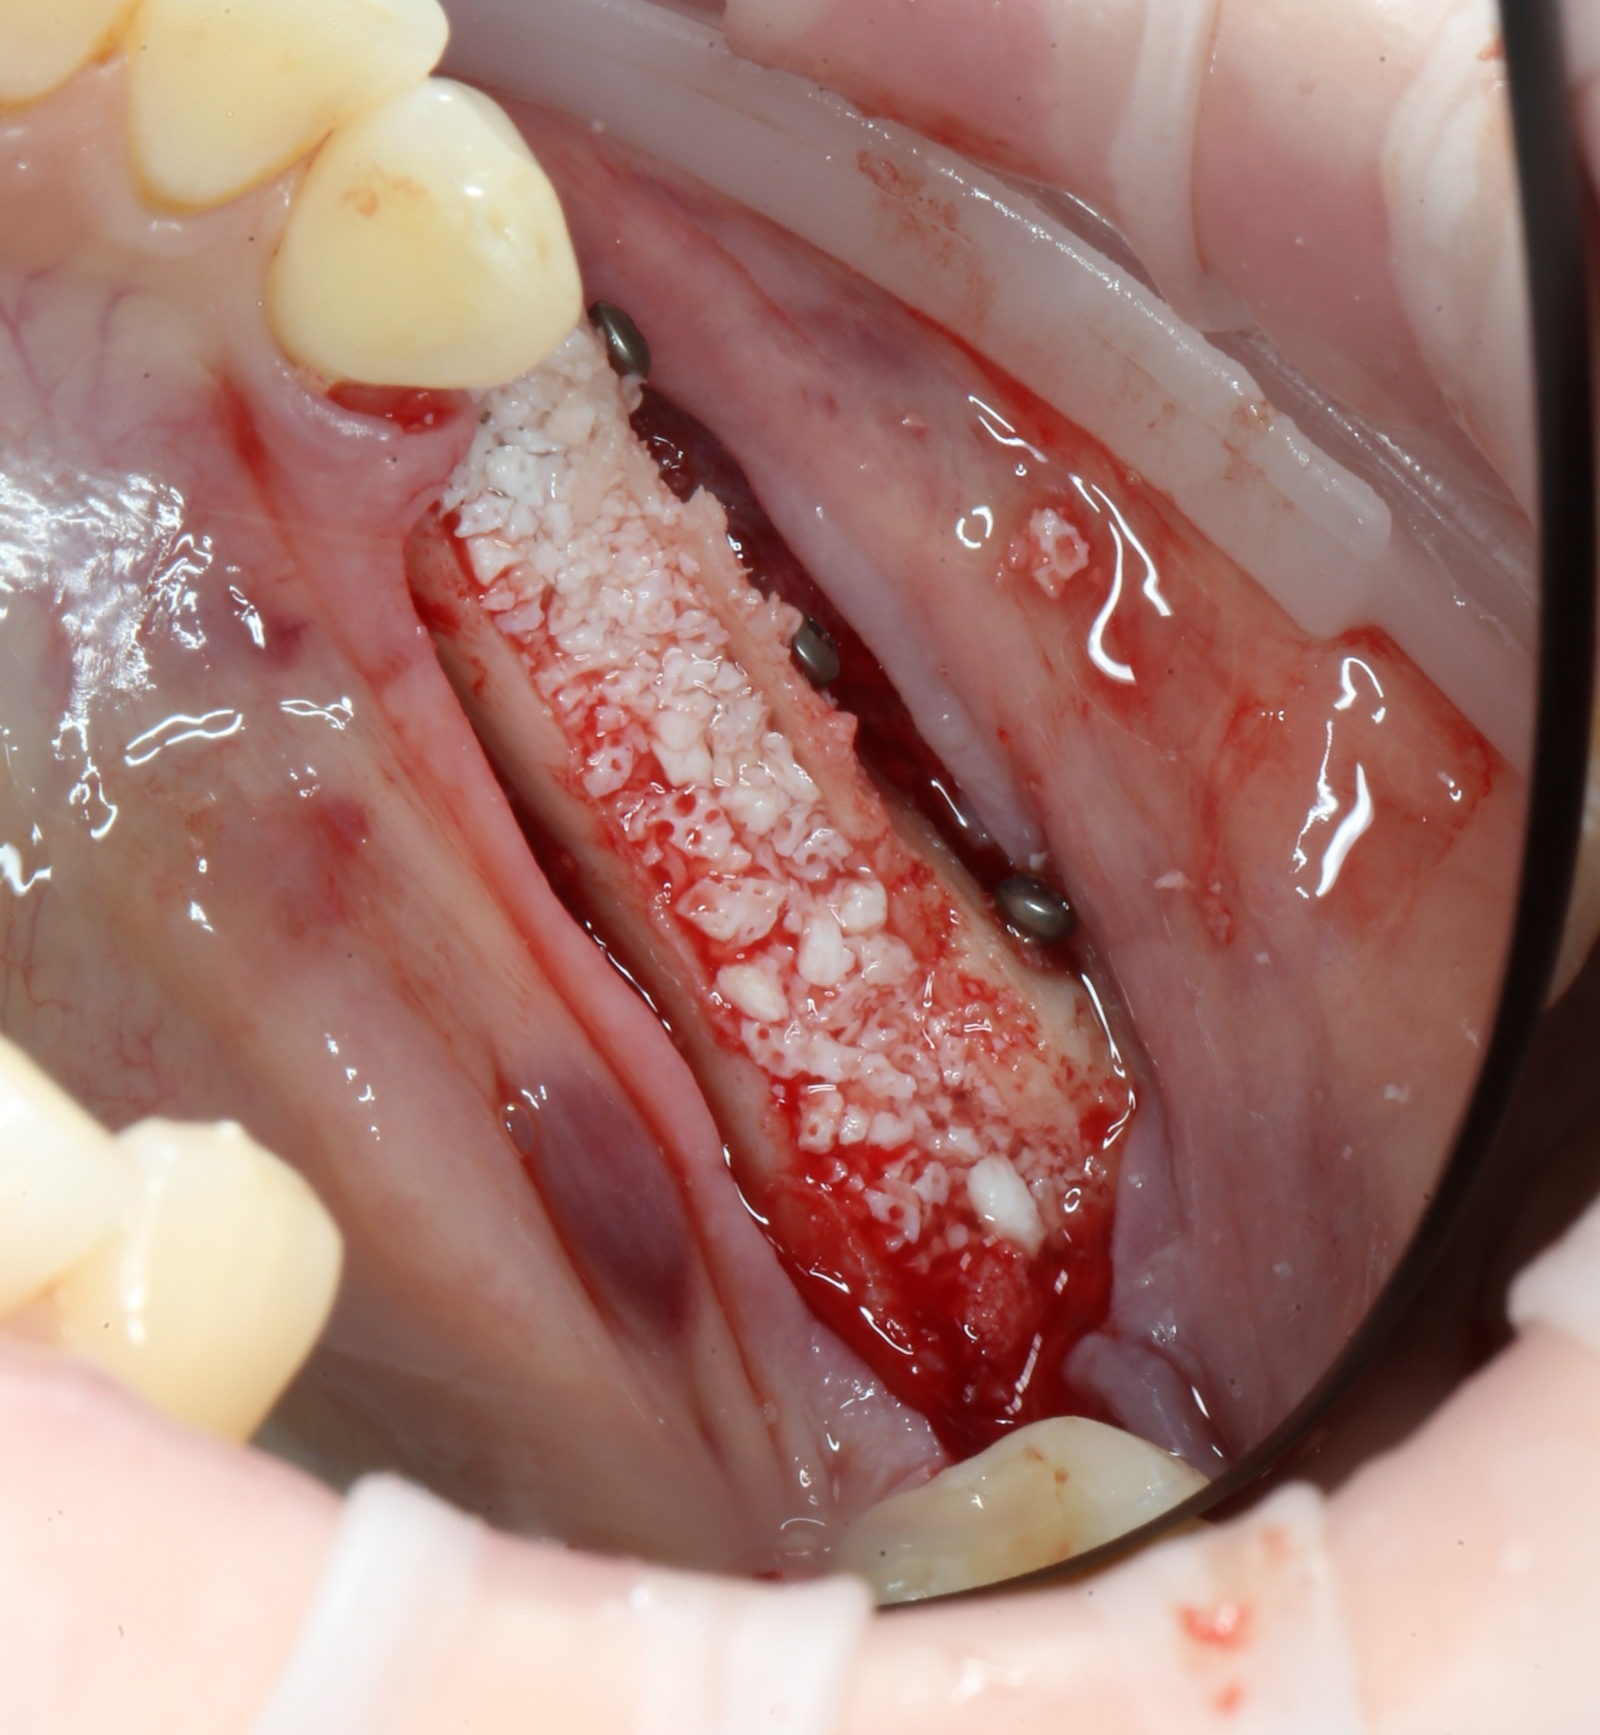

Далее необходимо заполнить промежуток между двумя фрагментами костным материалом.

В данном случае будет достаточно искусственного:

Содержимое баночки высыпается в «пиалу» и смачивается физ. раствором:

После чего распределяем костный материал:

Мягкая ткань восстанавливается намного быстрее, чем костная. Для того, чтобы десна не проросла сквозь костный материал, его необходимо укрыть специальной рассасывающейся мембраной:

Мембрана помещается между десной и костью, добавляются остатки костной стружки:

И весь этот бутерброд укрывается ею, как одеялком: